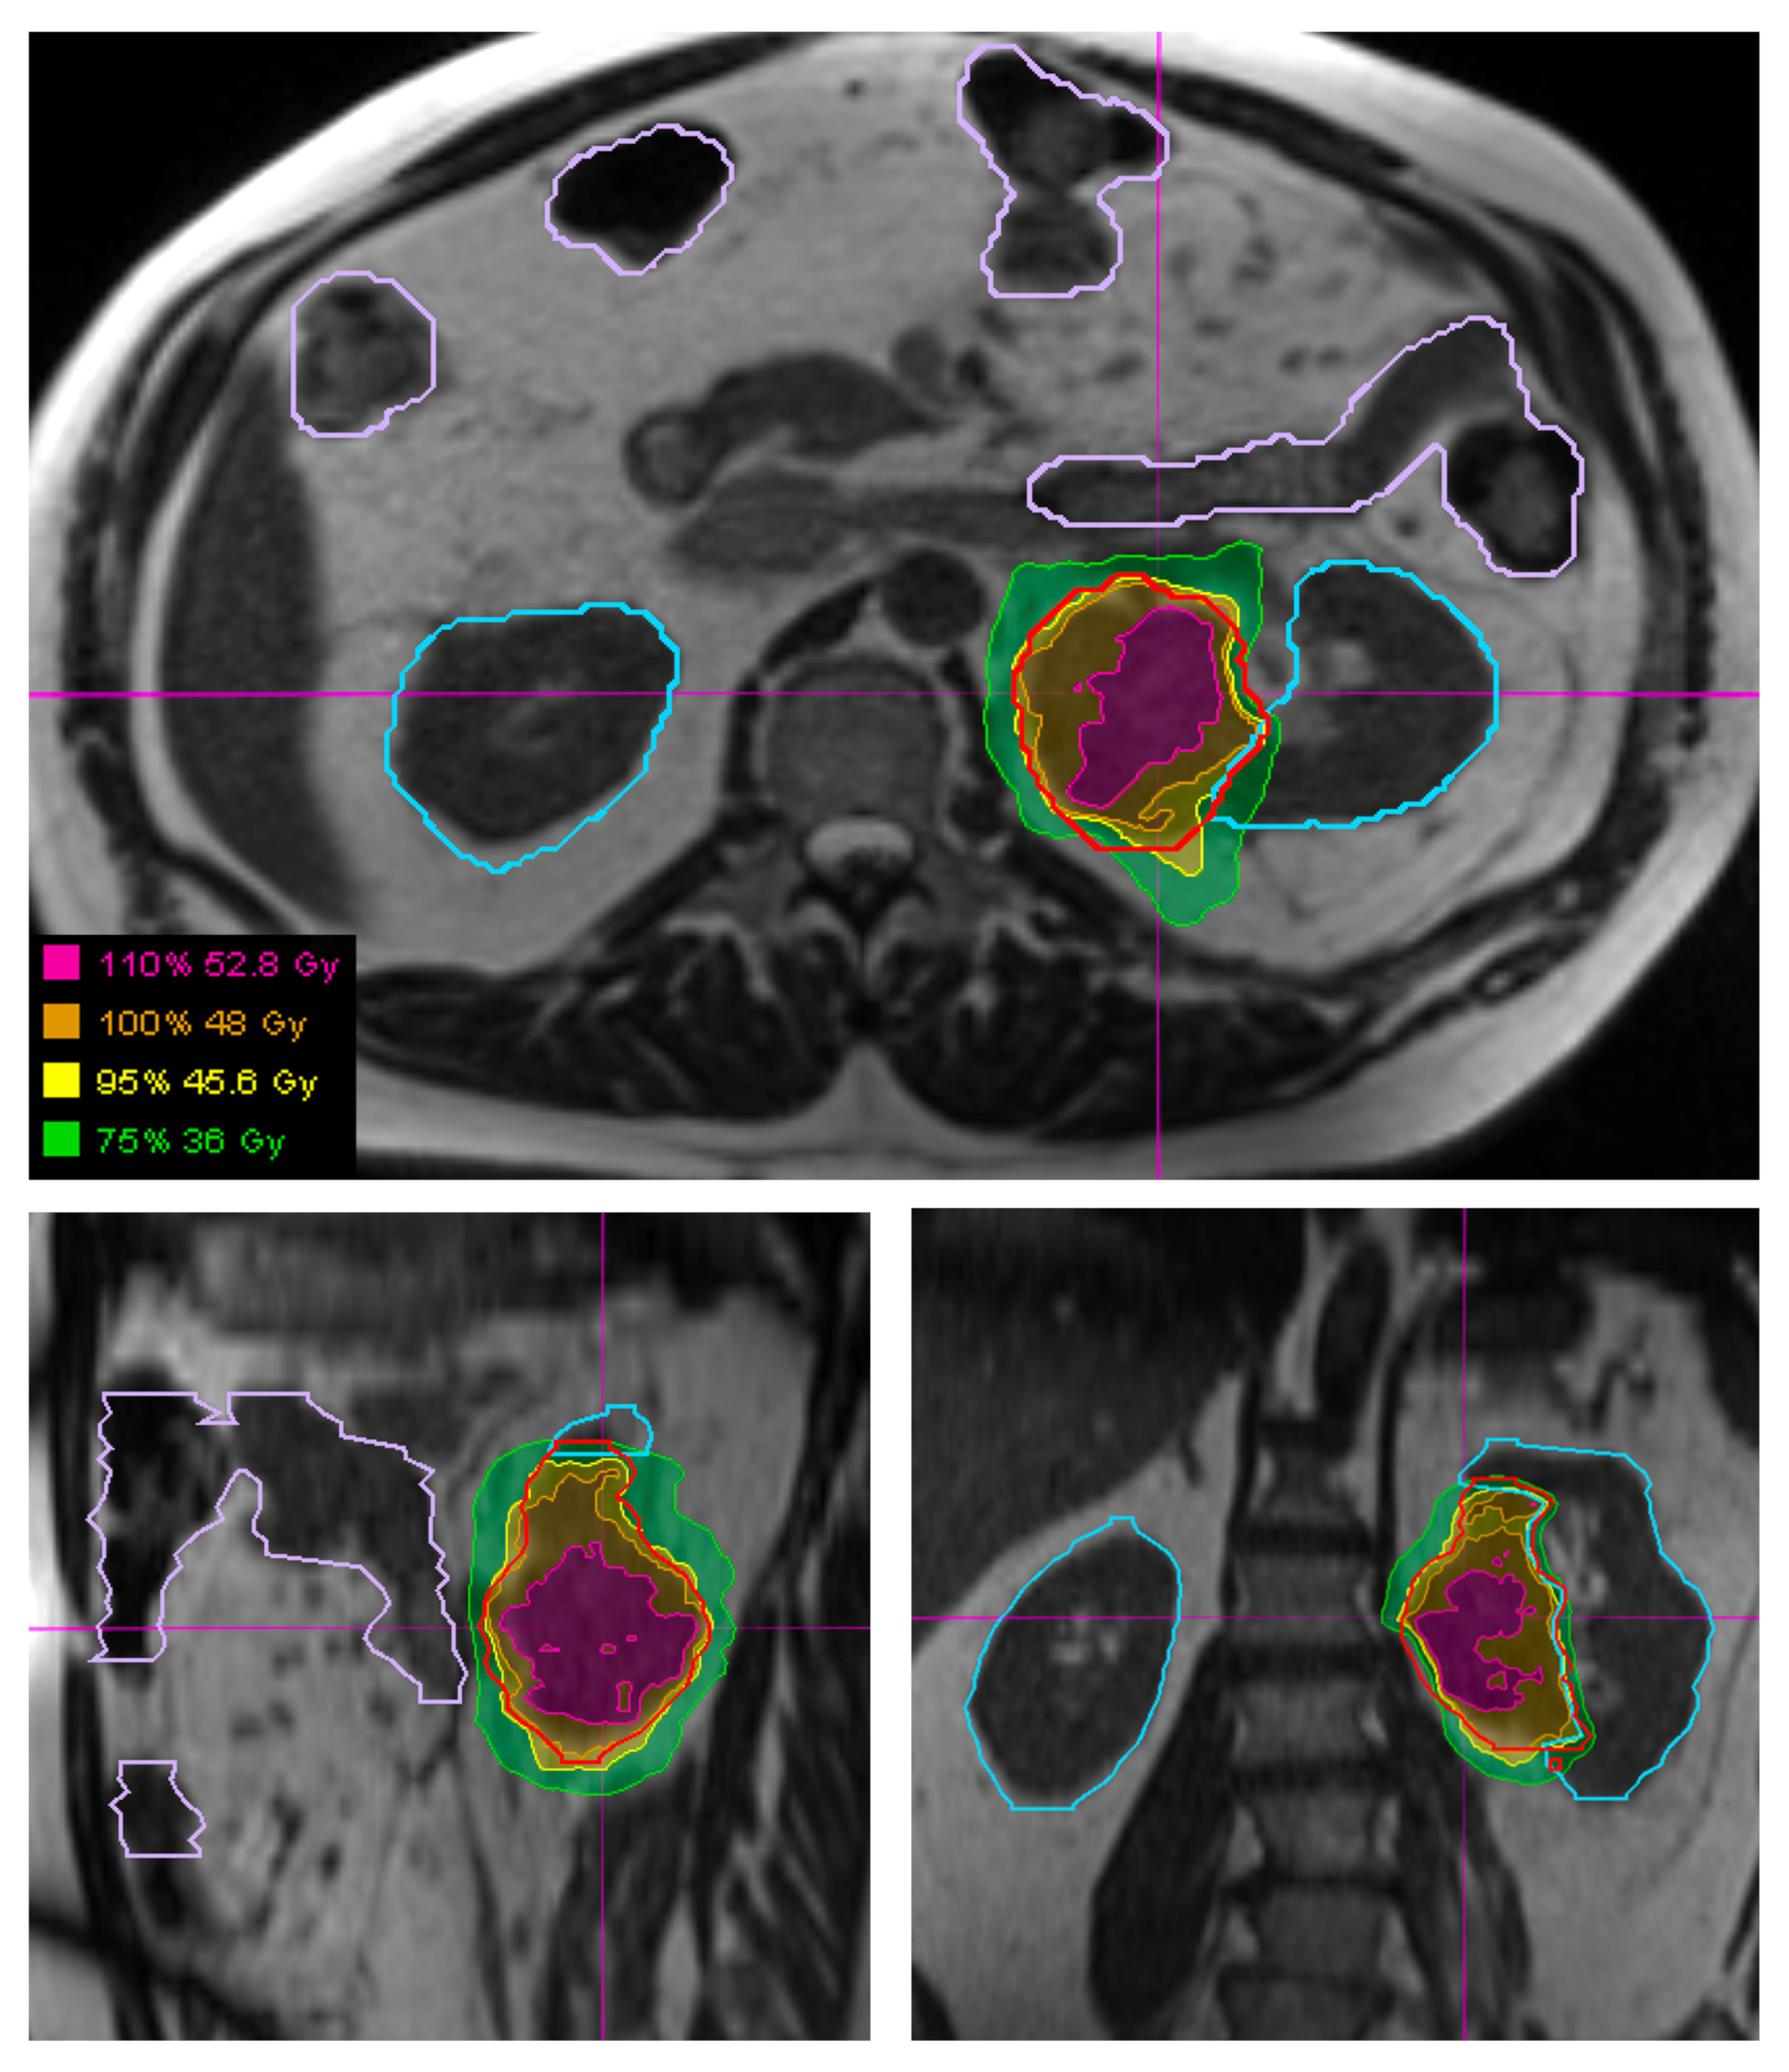

Figure 3. Visualization of a retroperitoneal STS (outlined in red) and surrounding organs at risk, specifically bowel (outlined in light purple) and kidneys (outlined in light blue), using the 3D True Fast Imaging (TRUFI) sequence on a MRI-guided linear accelerator. Hypofractionated radiation plan showing the plan which was adapted each fraction to optimize bowel and kidney sparing.

Here, we describe three cases of STS that were treated on a phase II clinical trial of hypofractionated radiotherapy for unresectable disease. Each patient had STS that was treated on an MRI-guided linear accelerator. One patient had STS in the upper extremity, one in the lower extremity, and one in the retroperitoneum. The patient with an unresectable upper extremity tumor had angiosarcoma histology with a target volume of 607 cubic centimeters (cc) and received 54 Gy in six fractions. The patient with an unresectable lower extremity tumor had dedifferentiated liposarcoma histology with a target volume was 2689 cc and received 48 Gy in six fractions. The patient with the unresectable retroperitoneal STS had spindle cell histology with a target volume of 81 cc and received 48 Gy in six fractions.

Daily MRI guidance allowed for the safe delivery of high dose hypofractionated radiation, with all patients having no grade 3 or higher acute toxicities. Understanding of potential late toxicity risks is still developing as clinical experience increases with this approach in patients with STS. For each of these patients, radiotherapy planning scans were acquired on 0.35T MRI (MRIdian, Viewray Inc., Mountain View, CA, USA) using a 3D True Fast Imaging (TRUFI) sequence, with 3 mm slice thickness and 40 cm × 40 cm × 43 cm field of view. A daily fractional MRI was acquired using the same imaging protocol to aid treatment set-up. In the case of the patient with STS of the lower extremity, MRI imaging enabled reproducibility of the positioning required to target the mobile lower extremity while avoiding the contralateral leg (Figure 1). In the case of the patient with STS of the upper extremity, MRI imaging ensured an accurate daily set-up and target delineation both for the planning and for each treatment (Figure 2). In the case of the patient with a retroperitoneal STS, daily MRI visualization allowed for adaptive planning which optimized tumor coverage while reducing dose to nearby organs at risk including bowel and kidney (Figure 3). Daily adaptation requires editing the OARs and/or PTV and re-optimizing the planned dose. Patients undergoing adaptive radiation are scheduled for 60 to 90 min. Based on the size of the lesion, editing contours may take approximately 10–20 min, re-optimization and plan review process may take additional 6–9 min.

In all cases, these large STS tumors were safely treated using hypofractionated radiation therapy. The patients with extremity STS had follow-up imaging demonstrating stable disease without local progression at 3 and 9 months for the cases of lower extremity STS and upper extremity STS, respectively. The patient with retroperitoneal STS had partial response on 6-month follow-up imaging. The use of MRI for daily set-up allowed for 0.3 mm PTV margins to be used for this patient, potentially decreasing the toxicity of the plan while affording confidence in tumor and OAR visualization and dosimetry.